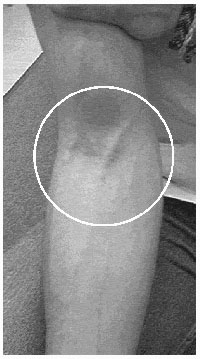

The Bloodbot is an active robot designed to take blood samples from the ante-cubital fossa (ACF) which is the area in the crease of the arm where the veins are close to the surface of the skin. It is the most common place from which to take blood samples.

The Bloodbot identifies the location of a suitable vein by pressing a probe against the surface tissue of the ante-cubital fossa and measuring the force on the probe. The difference in the characteristics of the tissue from its surroundings, in response to the applied force, indicates the presence of a vein.